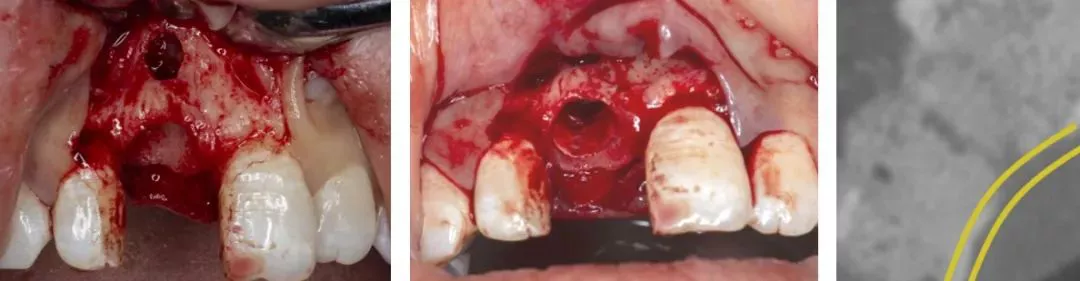

第三阶段:全程数字化引导下的手术实施

·      全程数字化手术导板引导下的种植手术。

·      术后CBCT显示种植体方向位置良好,唇舌侧骨壁完整。

·      术后pick up即刻修复。